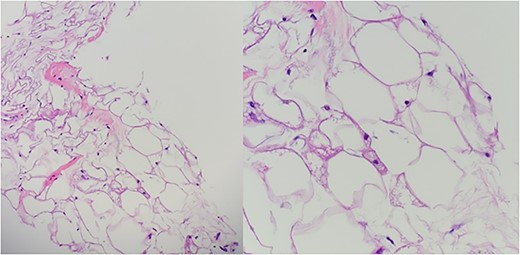

In the emergency department, vital signs were remarkable for elevated blood pressure of 166/81, but otherwise stable and afebrile. WBC count was elevated at 15.4 with left shift and hemoglobin was low at 9.6. Complete Metabolic Panel was notable for hyponatremia of 128, and mildly elevated BUN/serum creatinine of 26/1.5 which was slightly higher than his baseline of 17/1.3. Liver function tests were unremarkable. UA showed likely UTI with positive esterase, high RBC/WBC and bacteria and protein. A CT of the abdomen and pelvis was done, showing a left non-obstructing kidney stone and a left retroperitoneal fat density with stranding along the left iliopsoas measuring 12.6 × 8.1 cm × 3.7 cm, which was described as possibly a part of infectious or malignant process (Fig. 5). Subsequently, patient’s prior CT scans were available to be reviewed and it showed the same lipomatous mass 9 years earlier. (Fig. 6). Given the patient’s symptoms of left lower extremity pain and the possibility that the mass was responsible, a CT-guided core biopsy was ordered for diagnosis to rule out a malignant process as operative intervention was being contemplated. Pathology report of the core biopsy showed lobules of univacuolated adipocytes divided by thin septa. There were frequent multivacuolated adipocytes with small round nuclei, reminiscent of brown fat cells. No enlarged hyperchromatic cells, mitotic figures nor necrosis are seen. The findings supported the diagnosis of the lipoma variant of hibernoma (Fig. 4). Given the chronicity of the mass, the near identical size over 9 years and the diagnosis made from core biopsy, it was determined that the hibernoma was not the likely source of the patient’s LLE pain and hence the mass was not excised.

The diagnostic criteria for hibernomas include a circumscribed, lobulated, grossly yellow-brown mass with cellular features of brown fat, including numerous small cytoplasmic vacuoles and eosinophilic granular cytoplasm [6, 9]. Hibernomas are polygonal cytologically bland cells with small and central nuclei, prominent nucleoli, with rare cytologic atypia and mitotic figures [6]. The conventional lipoma in contrast to hibernomas are tumors with differentiation toward white fat cells [12]. The lipoma-like hibernoma variant has copious amounts of univacuolated cells mixed with scattered few granular multivacuolated hibernoma brown fat-like cells [8].